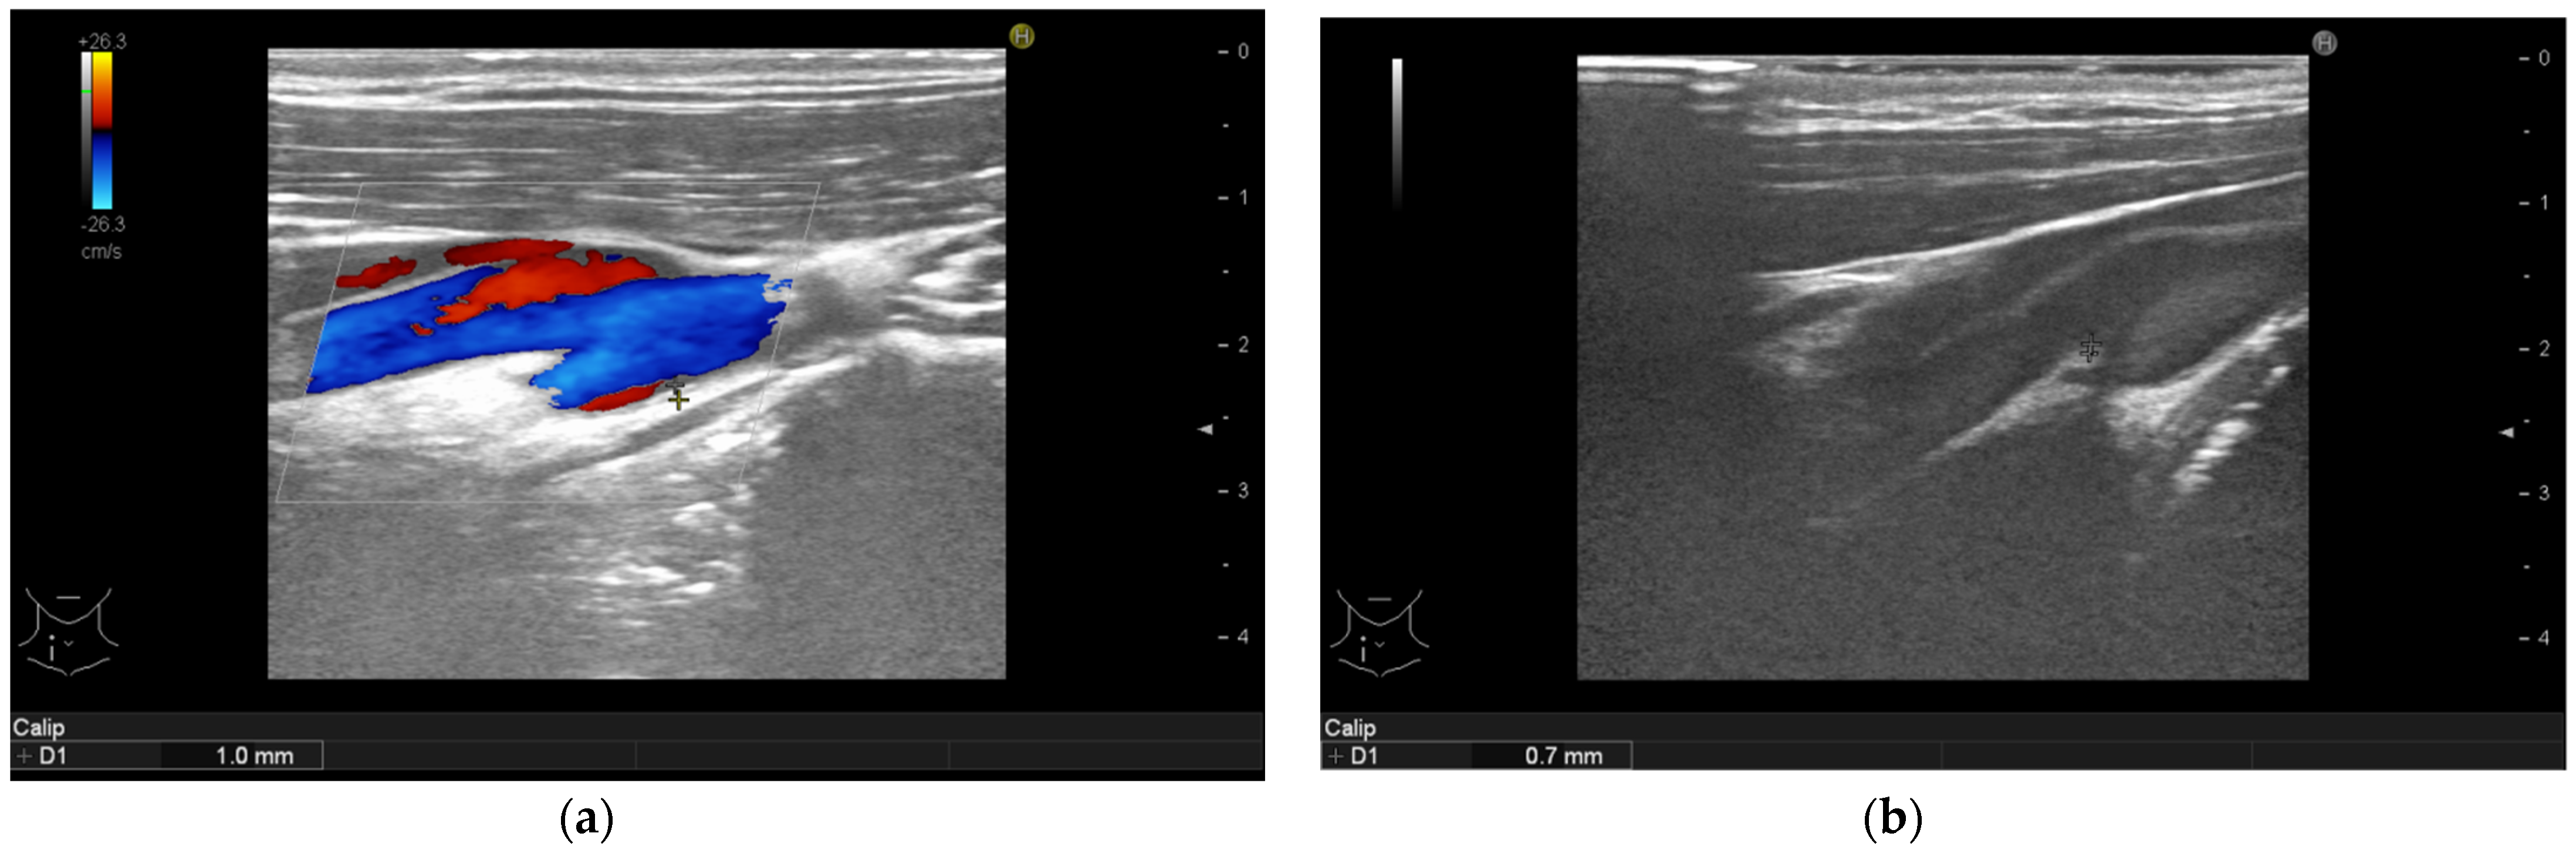

3.4. Ultrasonographic Findings

| Arterial Intima Media Thickness | Baseline Median (IQR)  | 6-Month Follow-Up Median (IQR) | p-Value |

| Intima media thickness of the right carotid arteries (mm) | 1.1 (1.0–1.3) | 0.8 (0.6–0.9) | <0.001 |

| Intima media thickness of the left carotid arteries (mm) | 1.1 (0.9–1.35) | 0.7 (0.6–0.9) | <0.001 |